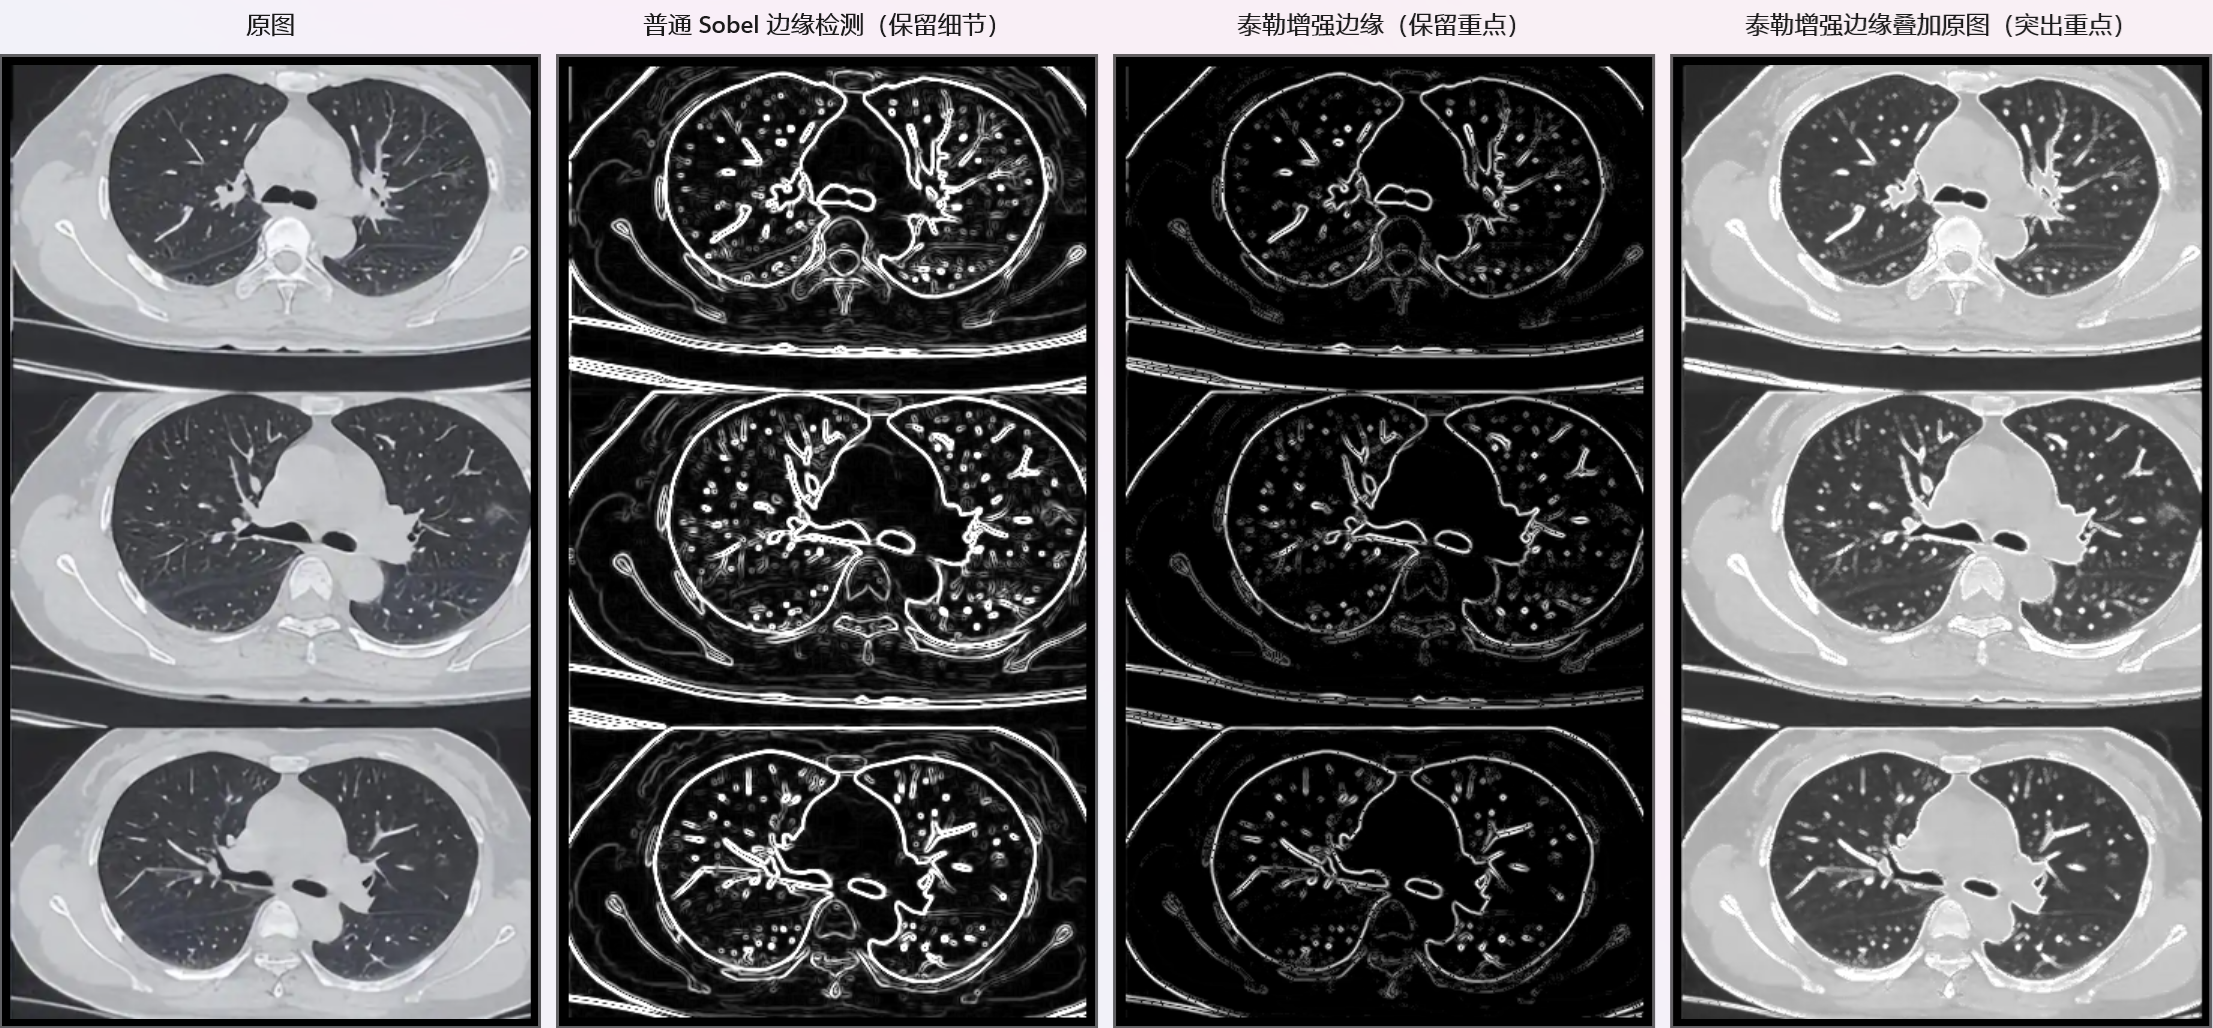

用泰勒级数做CT图像边缘检测,对比了 普通Sobel边缘检测 和 泰勒增强边缘检测 ,核心处理:

比对效果如下:

**Sobel检测:**只用到了一阶亮度变化率,所有细节全保留------包括物体轮廓、图像颗粒、传感器噪声,线条密密麻麻,有"流光感",艺术风格很强,但杂乱无章;

**泰勒增强:**结合了一阶变化率+二阶曲率,线条明显变少,很多细碎细节消失了,轮廓反而更突出、更干净。

泰勒增强怎么"丢了这么多细节"?这正式它的 "实用" 目标。

泰勒增强边缘,主动舍弃噪声细节,只强化稳定的真边缘, 线条干净,轮廓突出。

但是 Sobel的保留细节算法也更具有艺术视觉美:

我们看到的泰勒增强边缘里"丢失的细节",恰恰是它的核心价值------舍弃噪声,抓住本质。因此,理论本身没有绝对的"好"与"坏",关键看工程上怎么"用"。